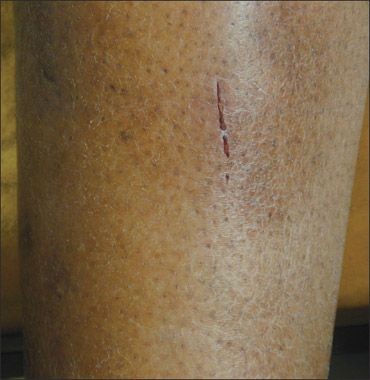

The patient’s condition, known as “winter itch,” occurs primarily in the very cold weather. This red plaque developed after she had habitually scratched the xerotic skin on her legs. The dermatosis usually occurs on the anterolateral aspect of the lower legs. Initially, the skin becomes dry and scaly, then red plaques develop from scratching. The erythematous skin can resemble cracked porcelain or “crazy paving.”